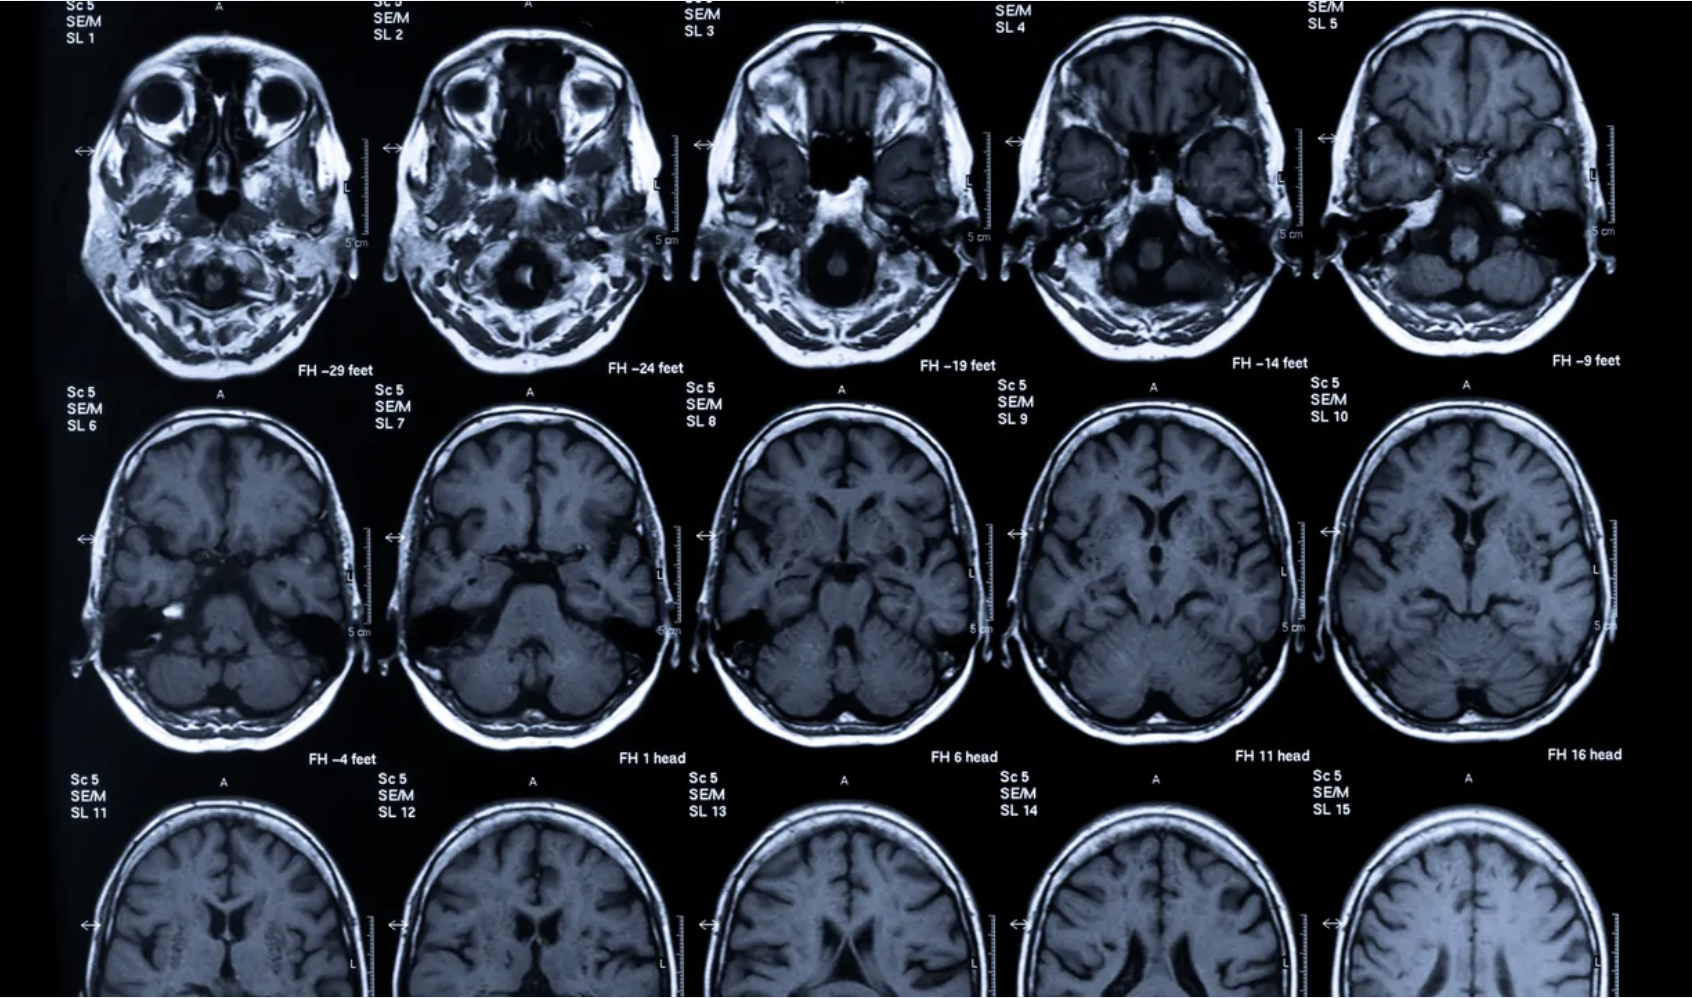

Objective neural measures, including neuroimaging and brain markers, to provide insight into functional brain states.

Our platform directly addresses these pain points and is designed to reduce trial failure risk by offering neuroimaging-based biomarkers that stratify patients and predict individual placebo or treatment response. Our biomarkers are grounded in robust neuroscience, clinically interpretable, and regulator-ready.